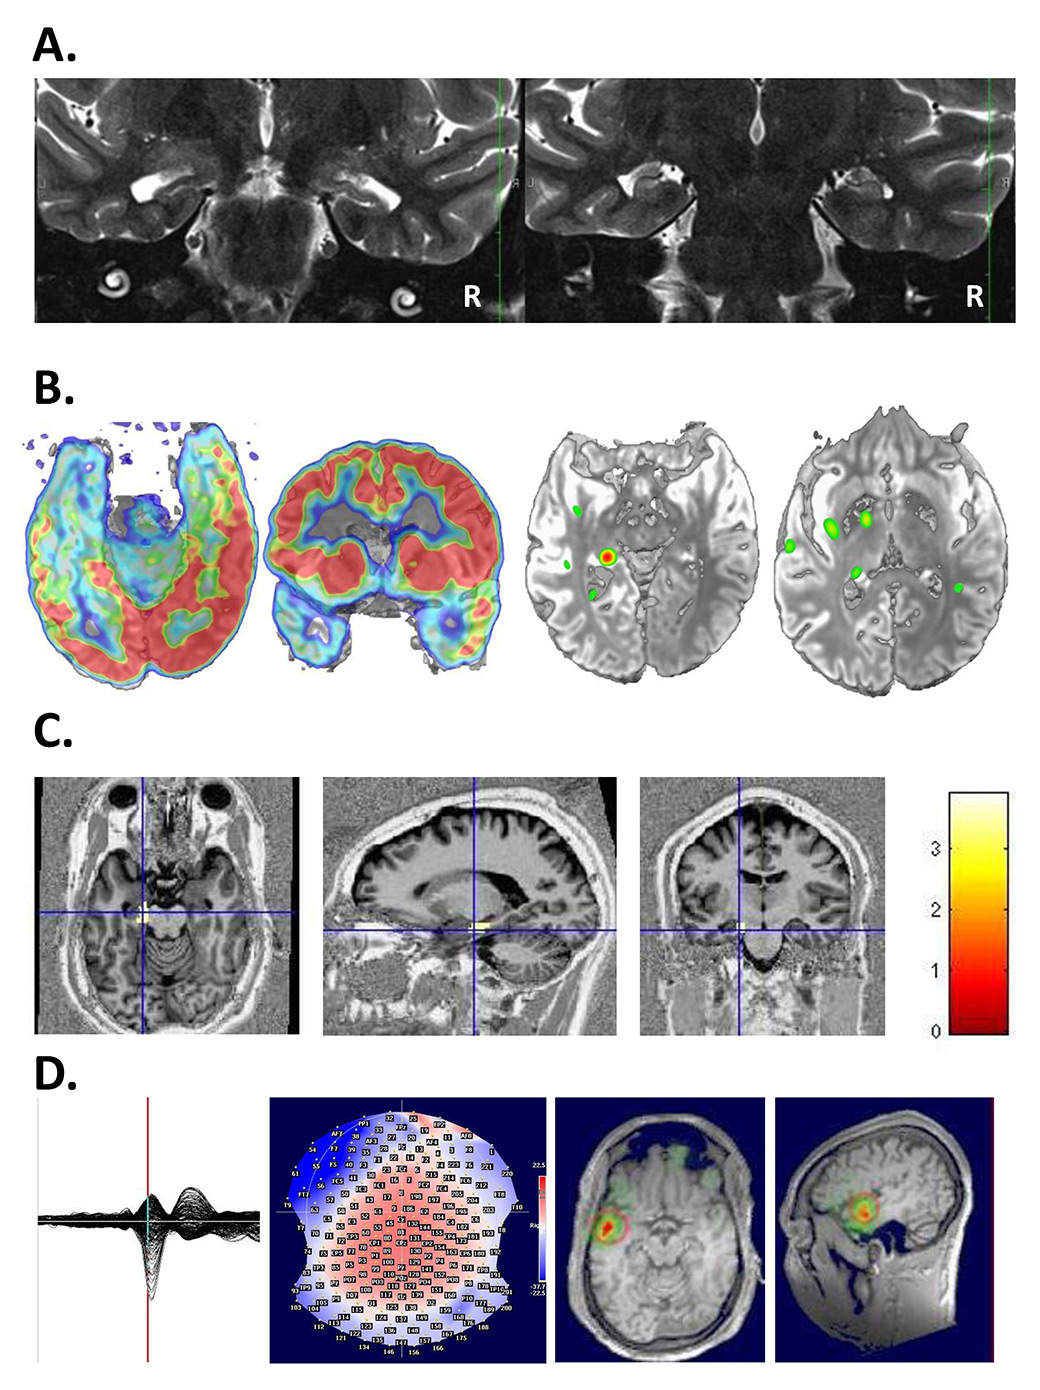

Surgical results depend critically on the definition of the ictal and interictal EEG onset zone as well as on the presence of a lesion in 1.5-Tesla or, better, 3-Tesla high-resolution MRI, obtained with an epilepsy protocol, i.e. 1 mm slices for most sequences, as detailed elsewhere [98]. If the lesion is highly suspected or functionally localised with PET, SPECT or ESI, but not visualised in the high-resolution MRI, additional statistical analysis of the MRI may be useful and unravel the underlying epileptogenic lesion [99, 100] (fig. 3).

Figure 3

A. 37-year-old patient presenting with seizures with a visual aura in the right visual field. On MRI a left occipital cavernoma was found (à), which was surgically removed (right). Work-up did not show any other focus or area of dysfunction. B. 34-year-old patient presenting with generalized seizures, EEG showed a very active focus in the right frontal lobe, but MRI was considered normal. Right: PET identified a focal hypometabolism in the right frontal lateral area (à). Left: Review of the MRI showed blurring between gray and white matter indicating the presence of a dysplasia.

EEG = electroencephalogram; MRI = magnetic resonance imaging; PET = positron emission tomography